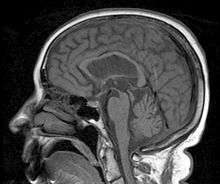

Progressive supranuclear palsy

Progressive supranuclear palsy (PSP; or the Steele-Richardson-Olszewski syndrome, after the physicians who described it in 1963) is a degenerative disease involving the gradual deterioration and death of specific volumes of the brain.[1][2]